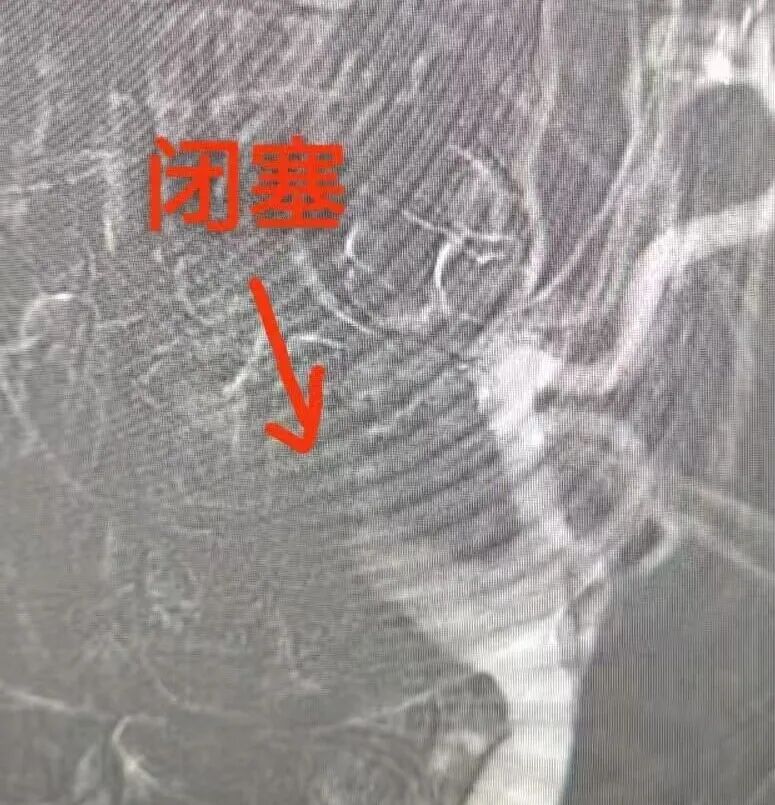

授权即行动!卒中中心绿色通道全程开启,患者第一时间接受静脉溶栓。与此同时,肖科金主任与朱胜华副主任医师迅速开展急诊血管内介入手术。造影证实“左侧颈内动脉急性闭塞”,团队立即行颈动脉再通,利用微导丝、球囊精准开通血管。术后影像显示:血流恢复通畅!